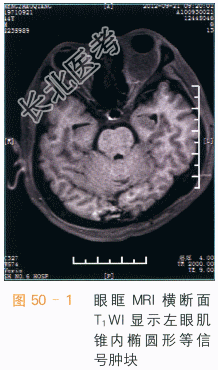

眼眶海绵状血管瘤CT表现为肌锥内类圆形边界清楚之占位,软组织密度,可见结节状钙化,注入造影剂后,呈渐进性强化,为该病的特征表现。肿块占位效应较轻,肿块较大时眼外肌受压向外侧移位,眼球向前方突出。MRI检查时,病灶的T₁WI信号和肌肉类似如图50-1所示,若有血栓形成,可表现为不规则高信号,T₂WI呈类圆形高信号,内偶可见细小低信号分隔,周围假包膜呈低信号,通常没有囊变或坏死如图50-2所示。MRI多平面扫描可以清晰显示肿块的边界,其与视神经、眼球、眼外肌分界清楚,见渐进性强化如图50-3、图50-4所示。